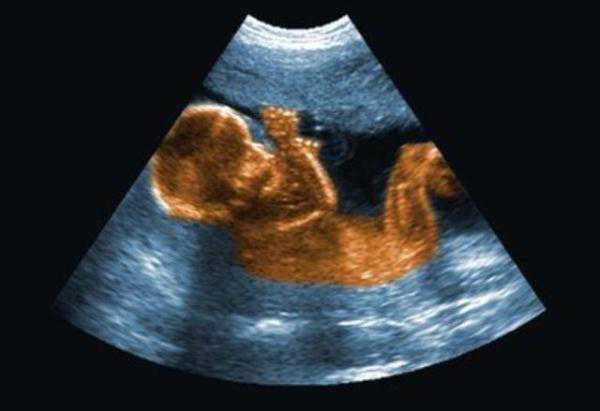

四维排畸检查,大约在怀孕第20~28周,最佳时间是22~26周。

在这些孕周范围内,胎儿在子宫内的活动空间已经有点小了,是无法伸展四肢的,所以宝宝只能将胳膊蜷缩起来,放在胸前,这时候手就会不自觉的挡住脸。

做四维彩超时,宝宝总爱捂着脸,对检查结果有影响吗?

所以进行四维彩超检查时,如若孕妇出现这样的情况,就可能会影响到检查结果。因此医生会要求孕妇多动一动,也要注意补充能量,比如说吃一块巧克力,或者是爬楼梯,多走动一下,宝宝就可能会将小手拿下来,然后继续进行检查。

如若宝宝一直不配合的话,那么医生可能会让孕妇下次改天再来做检查。所以说宝宝用手挡着脸是会影响到检查结果的。